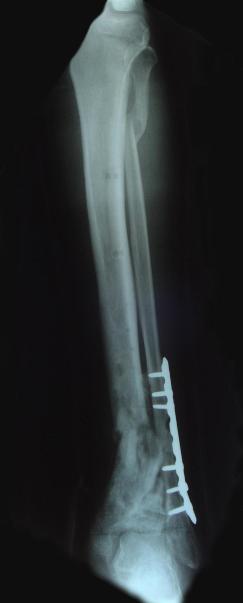

Post-corrective surgery X-Rays of the damaged right & left legs / ankles

The first two x-rays show Liam’s left ankle and pelvis prior to the accident. For comparison purposes it is interesting to see the

differences. The next x-rays were taken after the corrective surgery performed by Dr. Armendariz. Noticed that Dr. Armendariz has used tibia

bracing and also aligned the bone fragments of the left leg so that they could heal in the proper orientation. The external fixation has been

removed and Liam’s left foot has been returned to a more natural alignment.